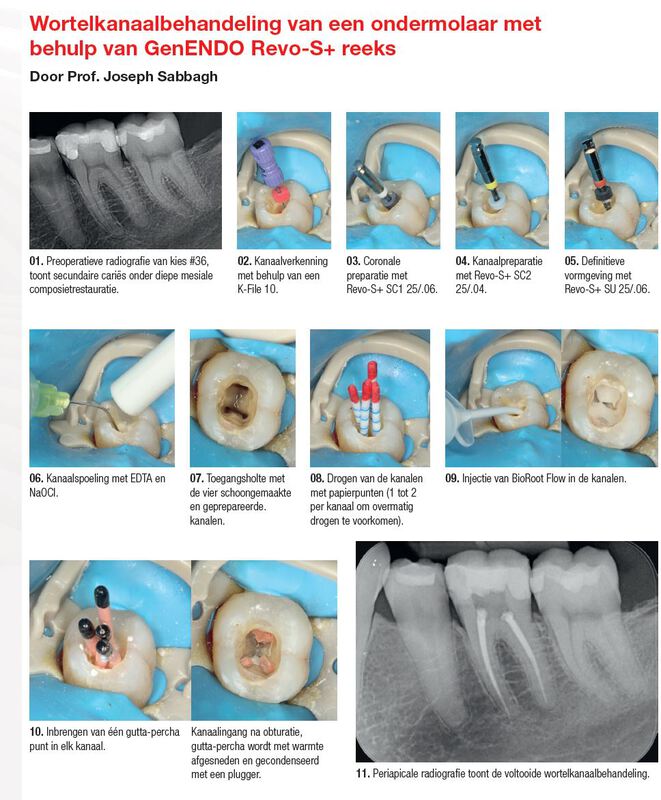

GenENDO K-Files